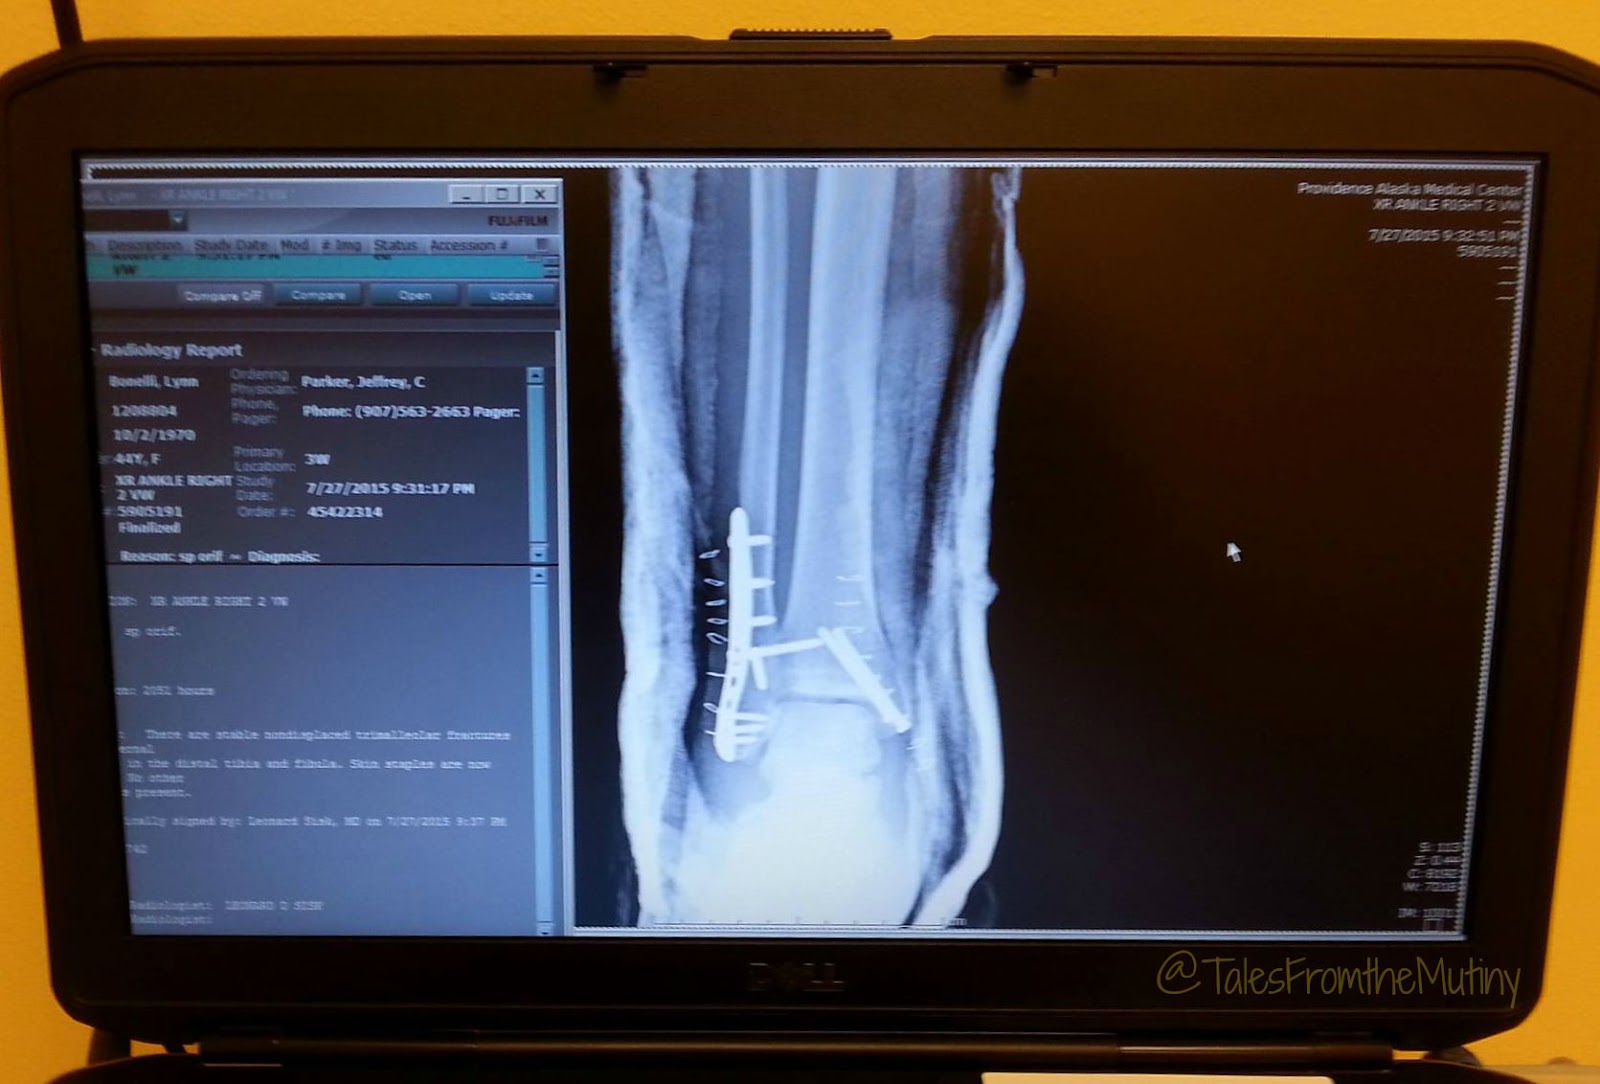

![]() |

| The x-ray showing the multiple fractures and severe dislocation. FYI: one’s ankle should not look like this… |

By early afternoon I was in a room and awaiting surgery. Clark had arrived and then went to get something eat and take a nap. The poor guy was working on less sleep than I was and he was still having to take care of everything. A little after 8pm, 24 hours after the accident, I was wheeled into the OR and underwent surgery where I received some screws and plates to hold my ankle together. A day later I worked with a physical therapist to practice with crutches, tackle some stairs and learn a few safe exercises which consisted of leg lifts, leg extensions, side leg lifts and leg curls on my stomach. I asked if I could add in a few simple yoga poses like cobra and updog (sans feet) and got the go-ahead. Two days later I was discharged with my very own crutches and a hundred ten pound splint.